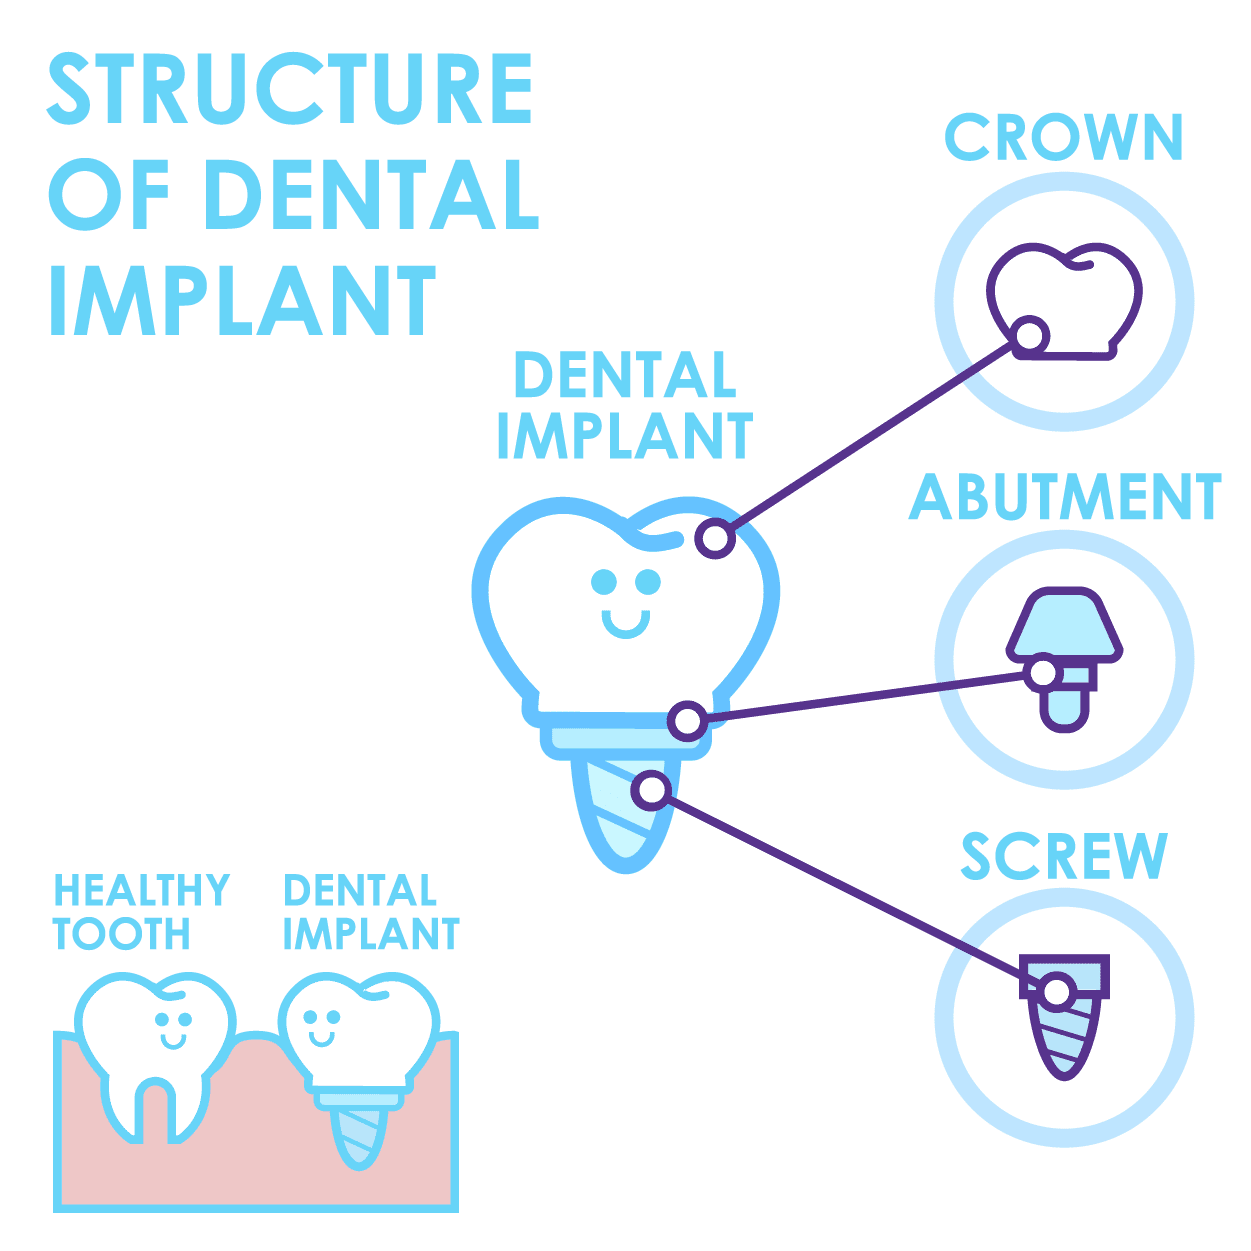

Dental Implants Explained

Dental implants come in many shapes and sizes but they can typically be broken down into three main parts; the crown, titanium abutment and the implant fixture. When these three parts are combined, they form the basic structure of a dental implant.

During implant surgery, the fixture of the dental implant will be inserted into the upper and/or lower jaw of the patient, this fixture will act as a replacement of a tooth’s root, bonding with surrounding bone over the course of a few months after the dental implant placement surgery.